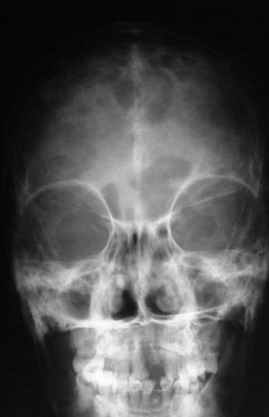

Уажаемые коллеги,представленные рентгенограмммы я показывал на нашем х-рей митинге - они были встречены с большим интересом.. Ну, ещё бы - я сам эту патологии встречал раза три за всю свою долгую жизнь:

VR> Кто шустрый - при какой патологии встречается так называемые <суставы Шарко>?

Сирингомиелия,

Травма спинного мозга

Опухоль

Т.н. нейрогенная артропатия бвает при диабете, периферических нейропатиях, заболеваниях спинного мозга... Как-то довелось вести больного с таким поражением тазобедренных суставов при третичном сифилисе.